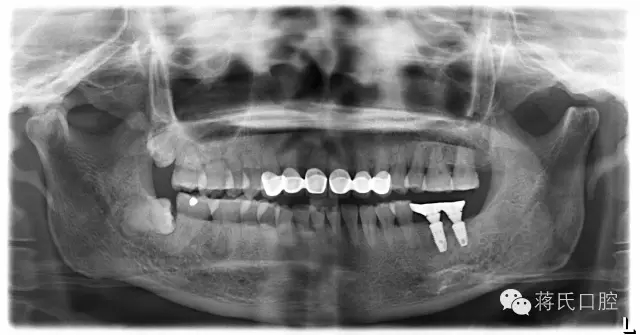

6.修复后全景片